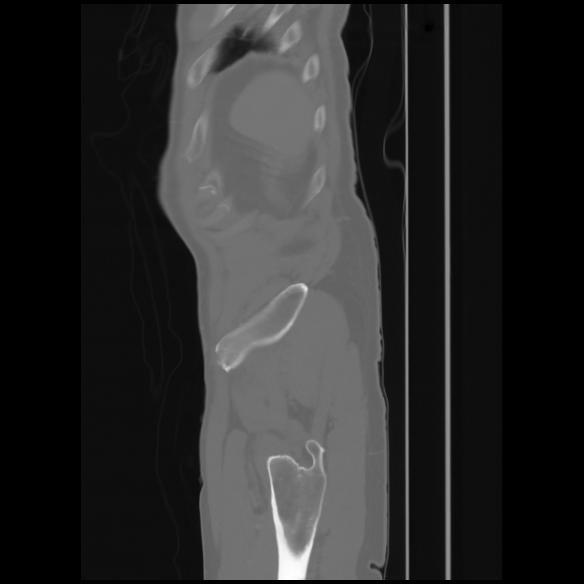

7 CUERPO,CE,Sagittal,3.000,CUERPO,Sagittal,